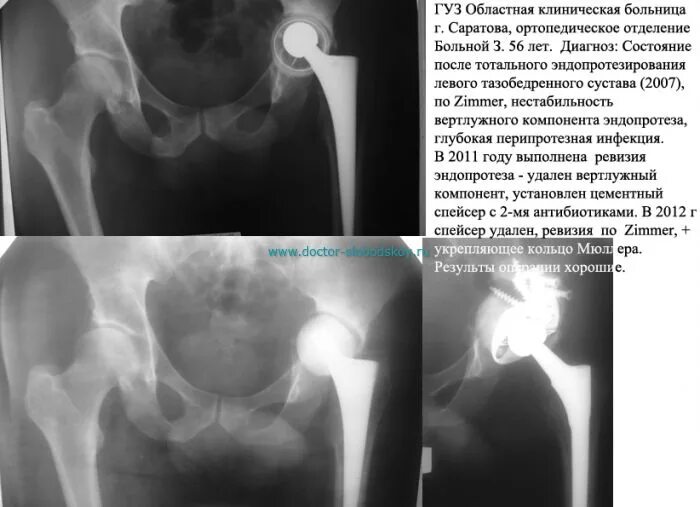

Почему после операции тазобедренного сустава